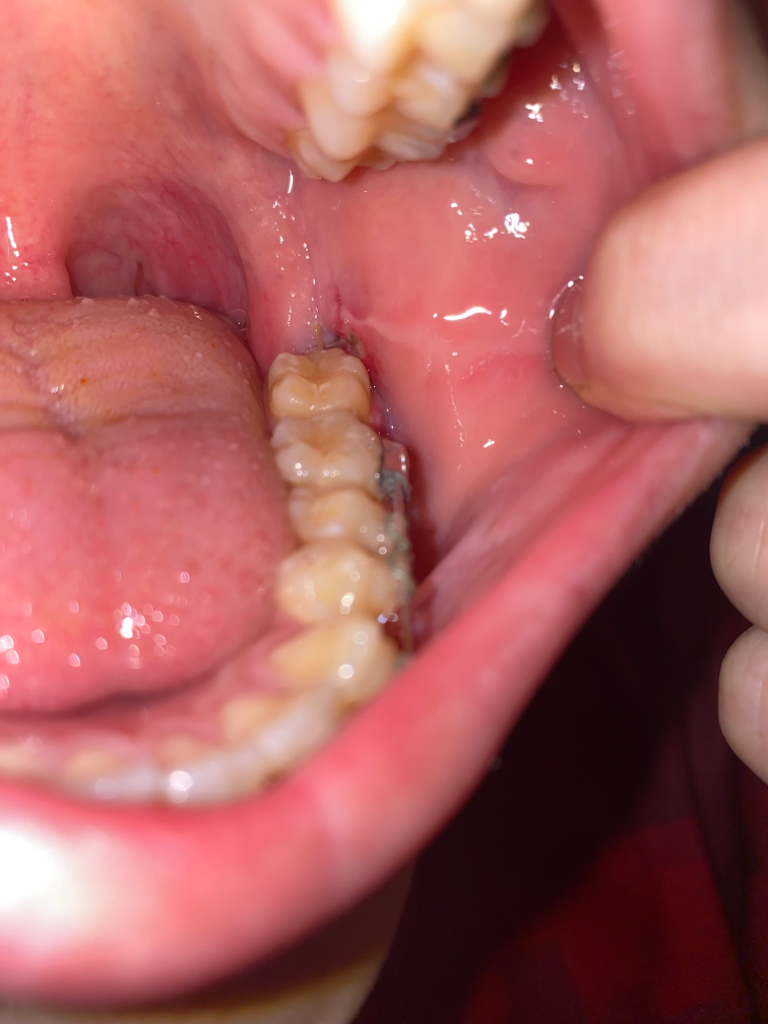

밥을 먹을때 혀를 움직이면 아프고 평상시에도 통증이있습니다. 통증이 그렇게 심하지는 않는데 어제는 거의 통증이 없다가 오늘 조금 다시 아프니 걱정이 되네요.

사진으로만은 드라이 소켁의 여부를 알기 힘듭니다.

드라이 소켓이 있는경우 통증이 심하고 냄새가 심하게 나게 됩니다.

사진 상으로는 정상적인 치유 과정으로 보이며 4일차에 약간의 통증이 있는 것은 정상적인 상태 이므로 걱정 안하셔도 괜찮습니다

혀나 손 등으로 발치 부위를 자극하지 않아야 하며, 가글 등을 사용해 해당 부위를 청결하게 관리하는 것이 좋습니다

드라이소켓은 극심한 통증과 악취로 응급실을 가야할 정도입니다. 걱정하실 필요 없습니다.